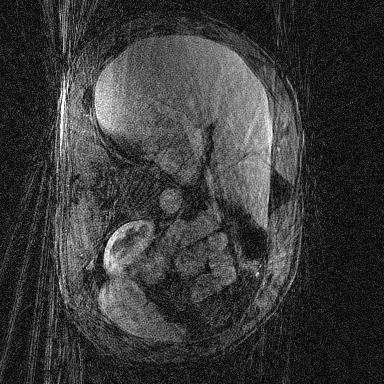

Supervised Deep-Learning (DL)-based reconstruction algorithms have shown state-of-the-art results for highly-undersampled dynamic Magnetic Resonance Imaging (MRI) reconstruction. However, the requirement of excessive high-quality ground-truth data hinders their applications due to the generalization problem. Recently, Implicit Neural Representation (INR) has appeared as a powerful DL-based tool for solving the inverse problem by characterizing the attributes of a signal as a continuous function of corresponding coordinates in an unsupervised manner. In this work, we proposed an INR-based method to improve dynamic MRI reconstruction from highly undersampled k-space data, which only takes spatiotemporal coordinates as inputs. Specifically, the proposed INR represents the dynamic MRI images as an implicit function and encodes them into neural networks. The weights of the network are learned from sparsely-acquired (k, t)-space data itself only, without external training datasets or prior images. Benefiting from the strong implicit continuity regularization of INR together with explicit regularization for low-rankness and sparsity, our proposed method outperforms the compared scan-specific methods at various acceleration factors. E.g., experiments on retrospective cardiac cine datasets show an improvement of 5.5 ~ 7.1 dB in PSNR for extremely high accelerations (up to 41.6-fold). The high-quality and inner continuity of the images provided by INR has great potential to further improve the spatiotemporal resolution of dynamic MRI, without the need of any training data.